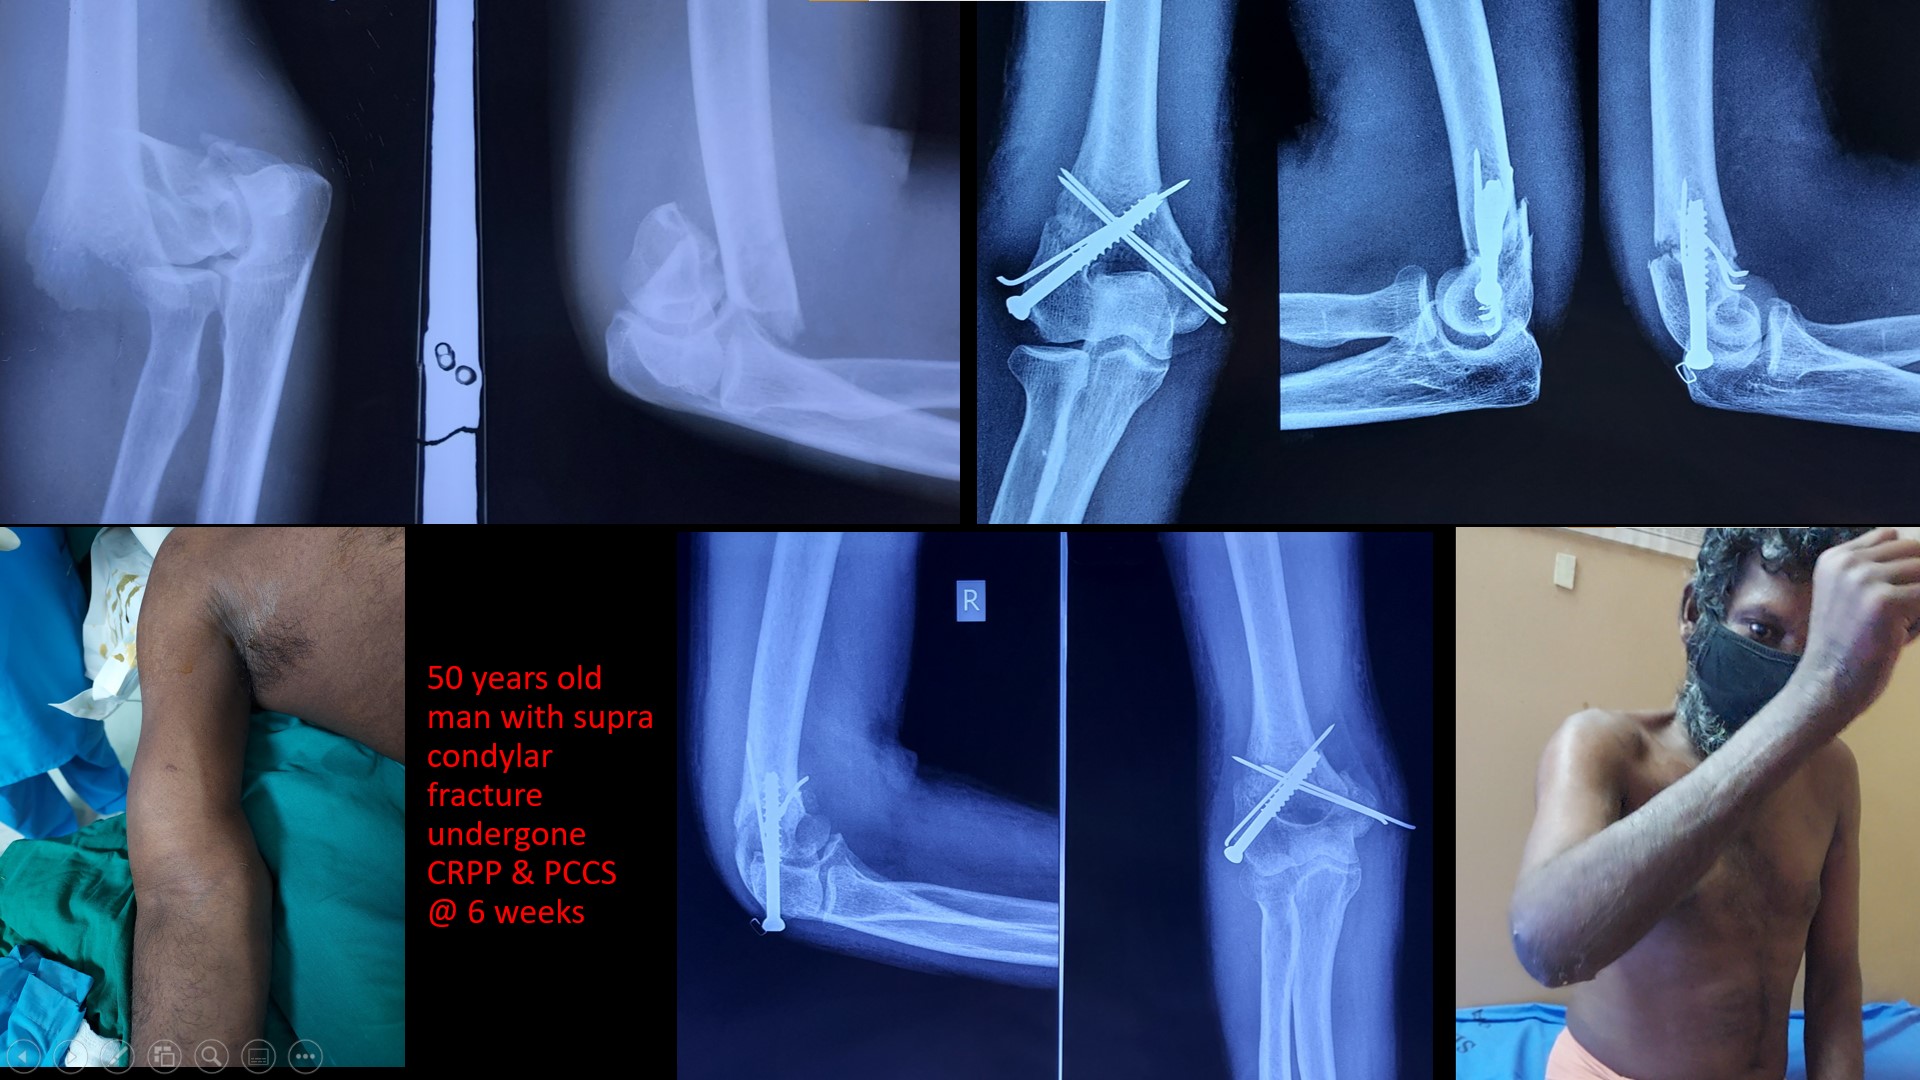

SUPRACONDYLAR #